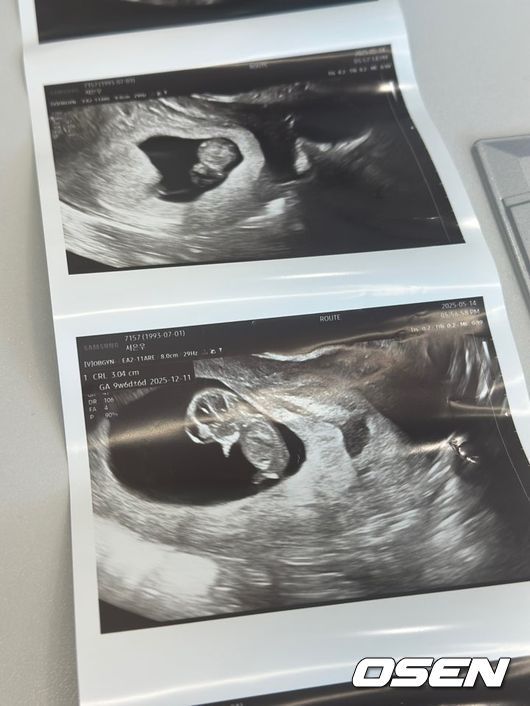

[OSEN=김채연 기자] 임신 소식을 전한 ‘하트시그널3’ 출연자 서민재(개명 후 서은우)가 남자친구이자 아기 아빠 A씨에 스토킹 혐의로 고소당한 가운데, 절박한 심경을 전하며 거듭 대화를 요구했다.

[사진] SNS